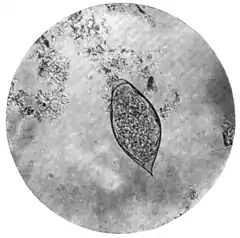

|style="padding-right:1em;"|Fig. 1.—Terminal-spined egg of Schistosomum hæmatobium.

(Microphotograph: Dr. Bell.) ||Fig. 2.—Lateral-spined egg of Schistosomum mansoni.